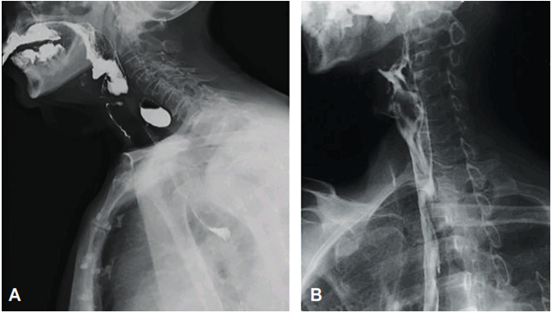

Hubo resolución de los síntomas en todos los pacientes, confirmándose la septotomía completa del tabique por esofagograma y endoscopia en la mayoría de ellos (Figura 2). No se presentaron casos de recurrencia y ningún paciente ha requerido reintervenciones.

El diagnóstico se puede realizar mediante un esofagograma, que determina el tamaño del divertículo y el diámetro del cuello, además evalúa la regurgitación y la aspiración 9. La tomografía computarizada puede ser un examen complementario para demostrar la presencia de un nivel hidroaéreo o del medio de contraste en la superficie del divertículo, pero la confirmación debe realizarse mediante una endoscopia digestiva alta 9.